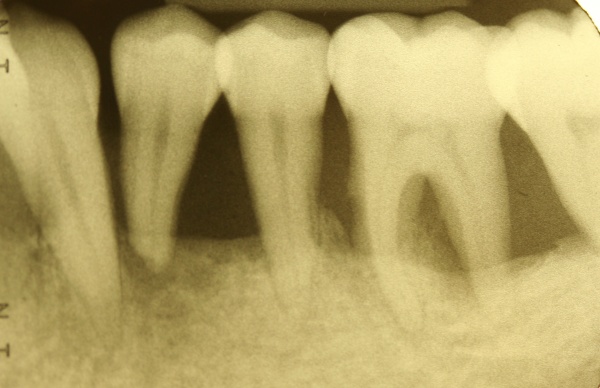

Diagnostische Parameter für die Beurteilung der dentalen und der periimplantären Zustände sind die Plaqueakkumulation, die Sondierungstiefen des Zahnes und des Implantates, Bluten auf Sondierung, Suppuration und der radiographische Knochenverlust (Salvi & Lang 2004). Unabdingbar ist im Minimum eine Sechspunktmessung (Sondiertiefen und klinischer Attachmentlevel). Immer wieder hört man von der Befürchtung, dass durch ein Sondieren des Implantates dieses geschädigt wird. In einer histomorphometrischen Studie an Hunden haben Etter et al. (2002) die Heilung des periimplantären Weichgewebes nach standardisiert klinischem Sondieren untersucht. Die Heilung des Epithelansatzes nach Sondierung des gesunden periimplantären Gewebes ist nach fünf Tagen abgeschlossen. Erfahrungsgemäß ist bei besonders aufmerksamem und vorsichtigem Sondieren ein äußerst geringes Verletzungsrisiko gegeben. Auch diese Techniken können in einem Praktikum bei einem Parodontologen aufgefrischt werden.